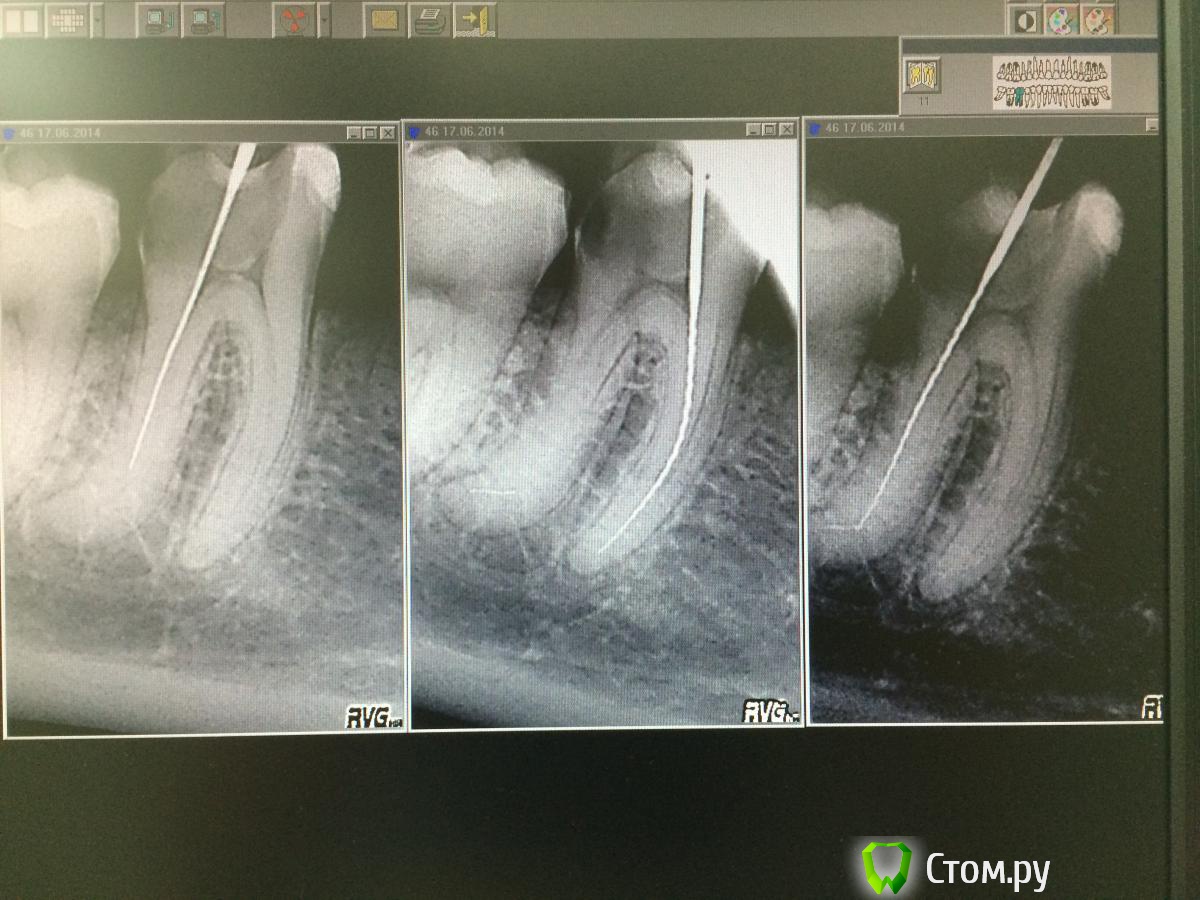

DimaKoleso Опубликовано 17 июня, 2014 Поделиться Опубликовано 17 июня, 2014 (изменено) Уважаемые доктора. Ситуация такая: пришла девушка с жалобами на накусывание на зуб. Раскрываю зуб 46, нахожу 4 устья, но проблема в том, что 2 из них очень узкие. И в итоге в дистальном щечном, на изгибе, сломался файл 10. Как поступить далее? УЗ нет, как можно достать. Изменено 17 июня, 2014 пользователем DimaKoleso Ссылка на комментарий

Kolchanov Опубликовано 17 июня, 2014 Поделиться Опубликовано 17 июня, 2014 Да, и, судя по снимкам, там крыша полости не снята. 1 Ссылка на комментарий

samsonov Опубликовано 17 июня, 2014 Поделиться Опубликовано 17 июня, 2014 (изменено) Вот и хочу узнать. Как дальше поступать?+1 к Колчанову. Дальше не стоит залезать в каналы, не раскрыв камеру. Изменено 17 июня, 2014 пользователем samsonov Ссылка на комментарий